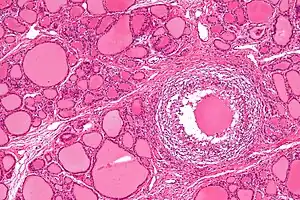

![]() | |

| Micrograph showing a granuloma in subacute thyroiditis. H&E stain. | |

De Quervain's thyroiditis, also known as subacute granulomatous thyroiditis or giant cell thyroiditis, is a member of the group of thyroiditis conditions known as resolving thyroiditis. People of all ages and genders may be affected.

Patients will experience a hyperthyroid period as the cellular lining of colloid spaces fails, allowing abundant colloid into the circulation, with neck pain and fever. Patients typically then become hypothyroid as the pituitary reduces TSH production and the inappropriately released colloid is depleted before resolving to euthyroid. The symptoms are those of hyperthyroidism and hypothyroidism. In addition, patients may suffer from painful dysphagia. There are multi-nucleated giant cells on histology. Thyroid antibodies can be present in some cases. The clinical presentation during the hyperthyroid phase can mimic those of Diffuse Toxic Goiter or Graves' disease. In such cases, a radionuclide thyroid uptake and scan can be helpful, since subacute thyroiditis will result in decreased isotope uptake, while Graves' disease will generally result in increased uptake. Distinguishing between these two types of disease is important, since Graves' disease and Diffuse Toxic Goiter can be treated with radioiodine therapy, but subacute thyroiditis is usually self-limited and is not treated with radioiodine.